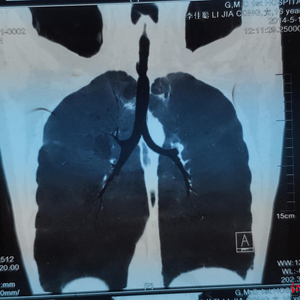

↑术前评估气管狭窄段较长

女孩入院后,治疗团队就着手进行病情评估。检查发现气管上段有3-6cm长度的瘢痕狭窄区域,此区域因瘢痕挛缩过重,用球囊扩张难以达到最佳效果。而且,患者将承受球囊扩张后气道破裂损伤甚至致命风险,因此手术切除是其唯一出路。